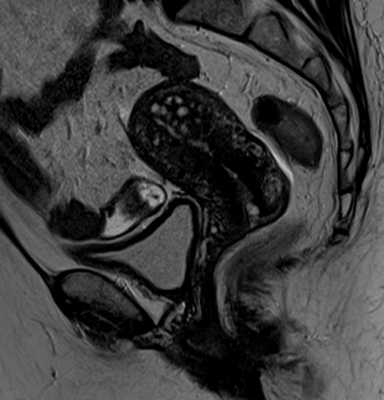

![]()

Рис.5: Фокальный аденомиоз: а) сагиттальные T2, b) аксиальные T2 , с) аксиальные T1 3D FS изображения, показывающие фокальное асимметричное утолщение переходной зоны, образующее плохо отграниченную область с низкой интенсивностью сигнала, наличием в структуре мелких гиперинтенсивных на Т2 и Т1FS включений, представленных мелкими кровоизлияниями.